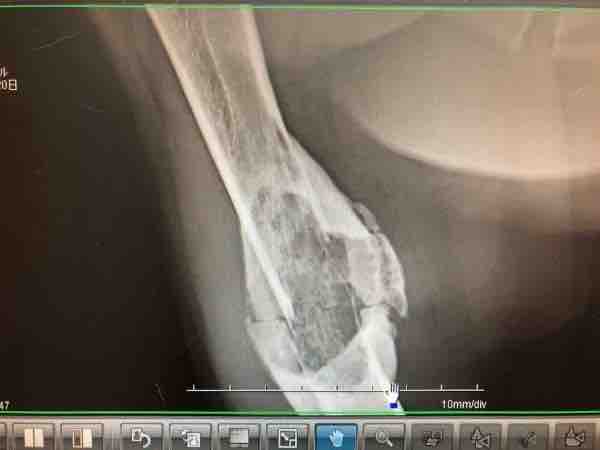

IMG_1073

骨折治療中だった脚が急にボコボコしてきたのが、6月(この写真は6/14)

この脚が…たったの2ヶ月で↓

IMG_1066

たったの3ヶ月でこんなに大きくなってしまいました

骨肉腫が大きくなるスピード、めちゃくちゃ早い